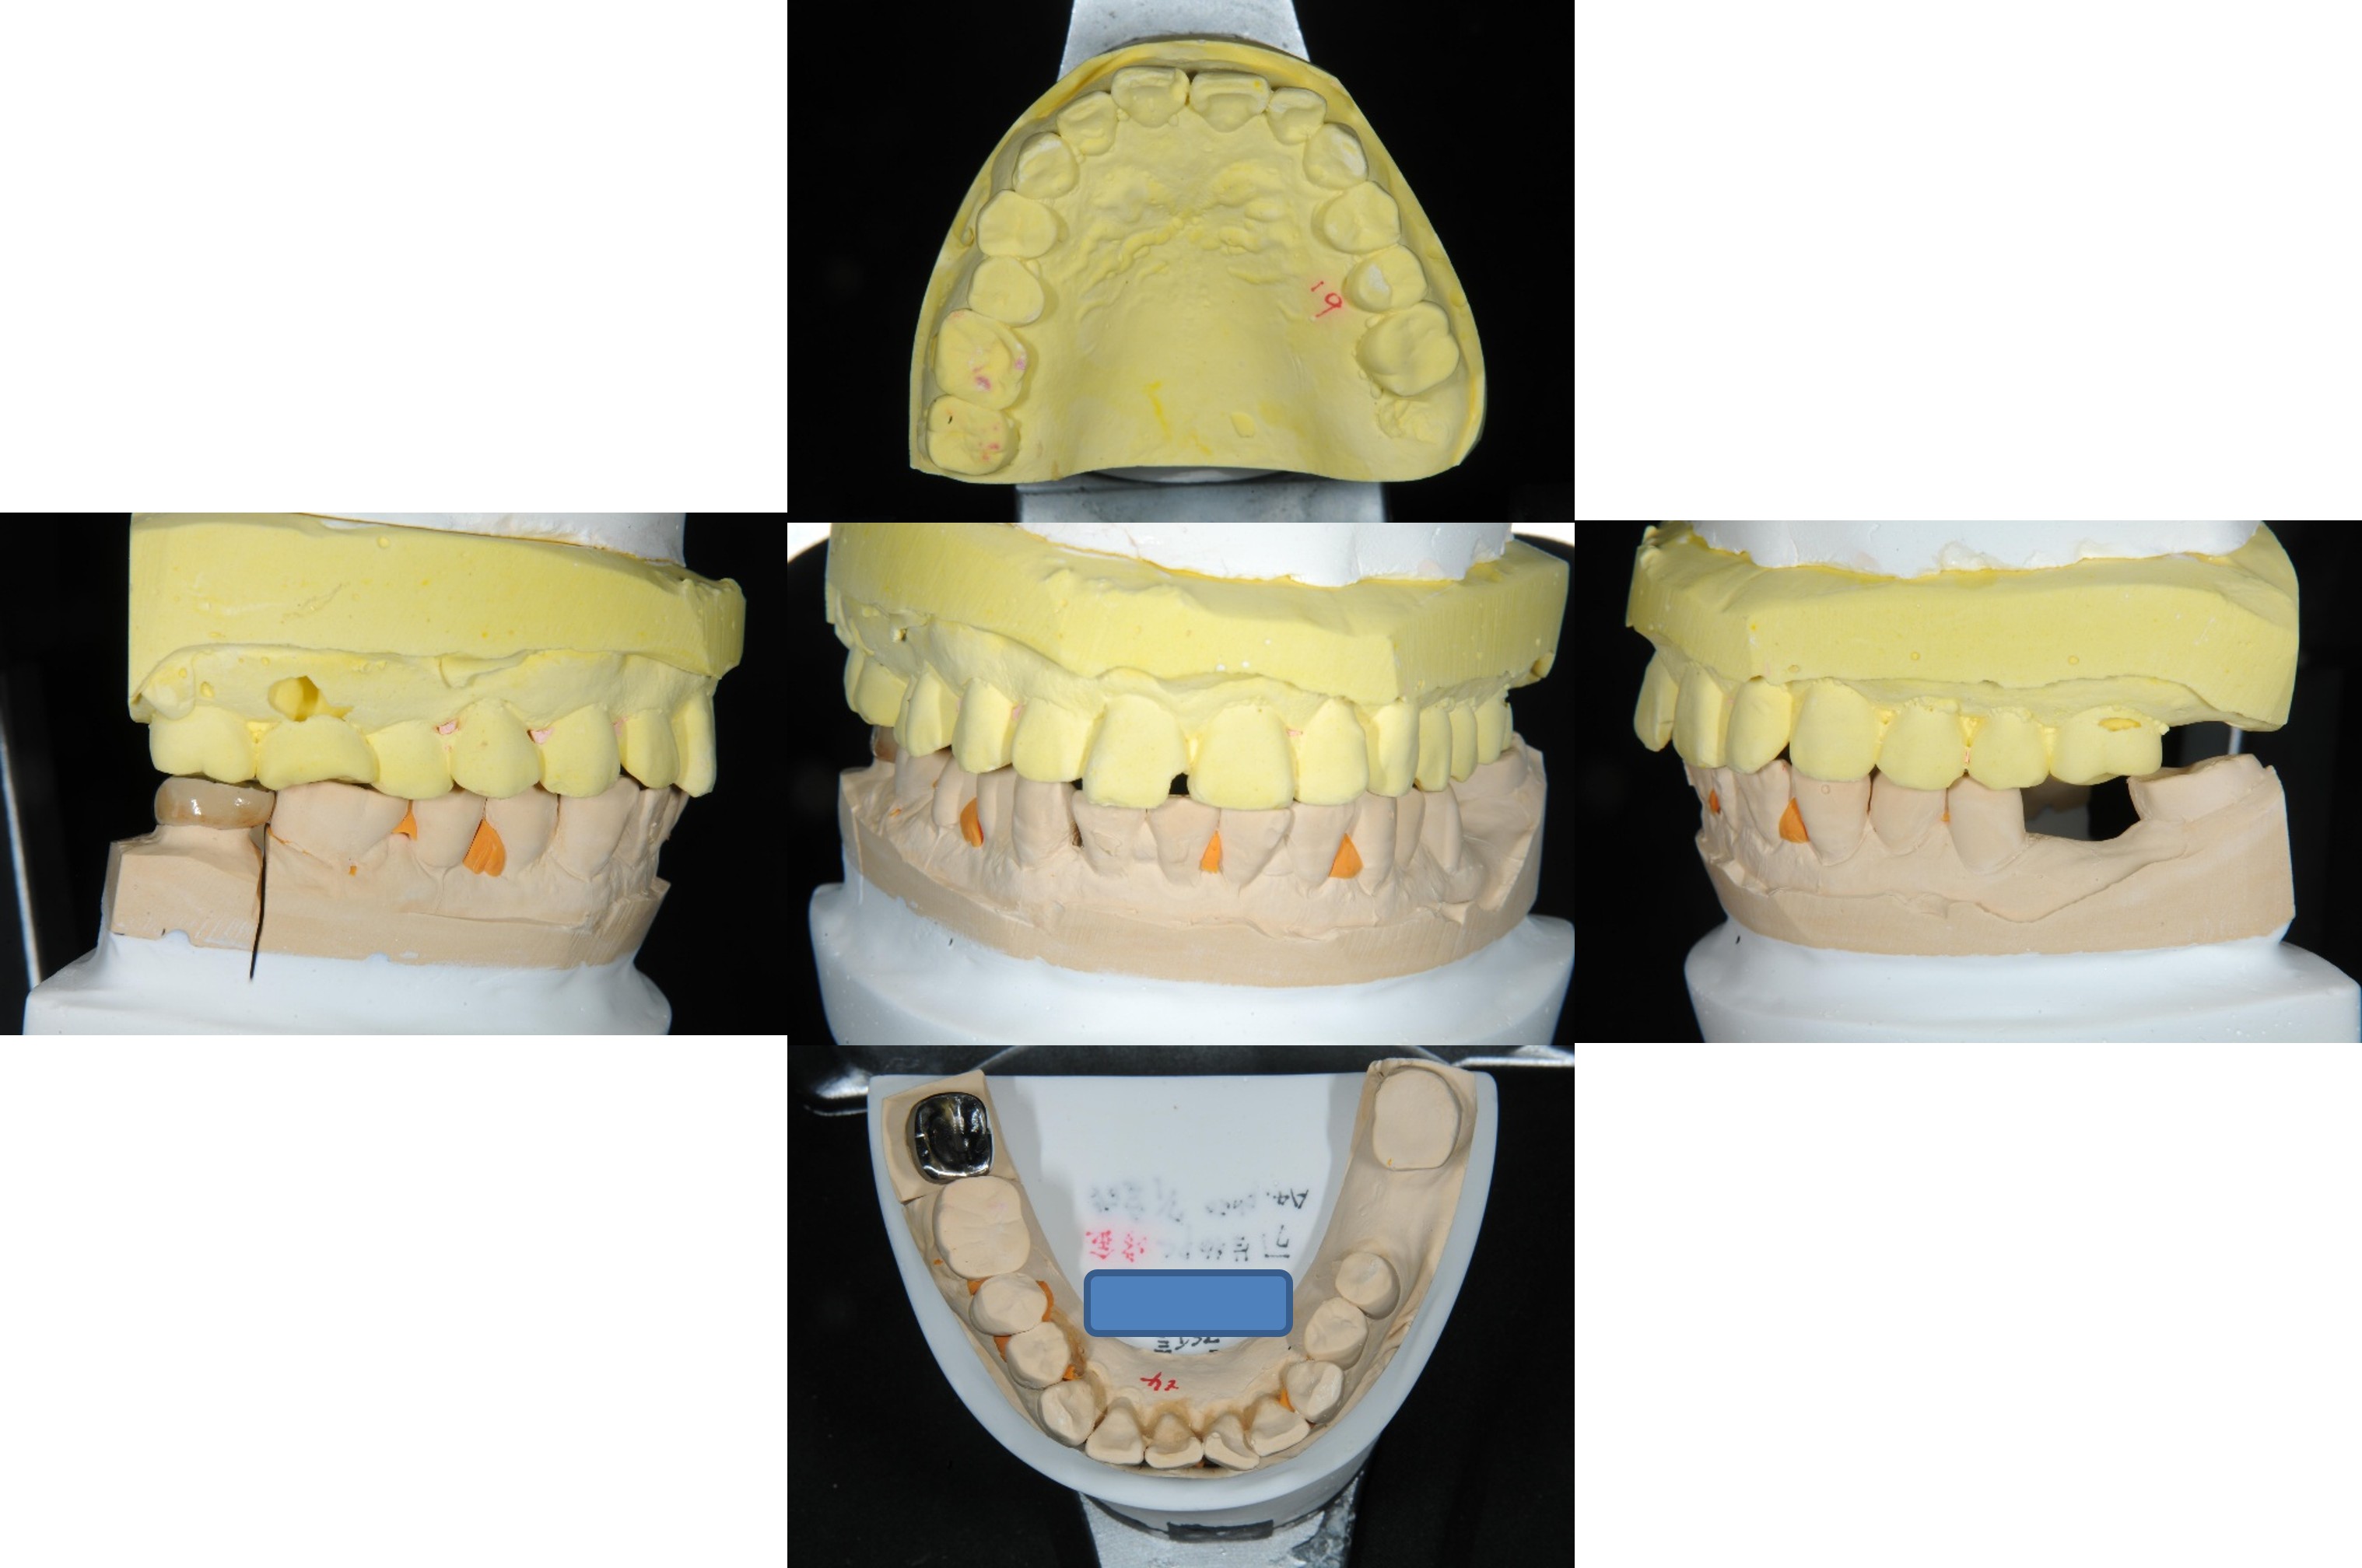

印模製作:等傷口癒合後,會為牙齒製作印模。

製作金屬燒付瓷牙:牙技師會根據印模製作出金屬燒付瓷牙,其外層是陶瓷,內層是金屬。

取面弓,上咬合器

製作固定假牙

因受力考量,製作金屬燒付瓷牙